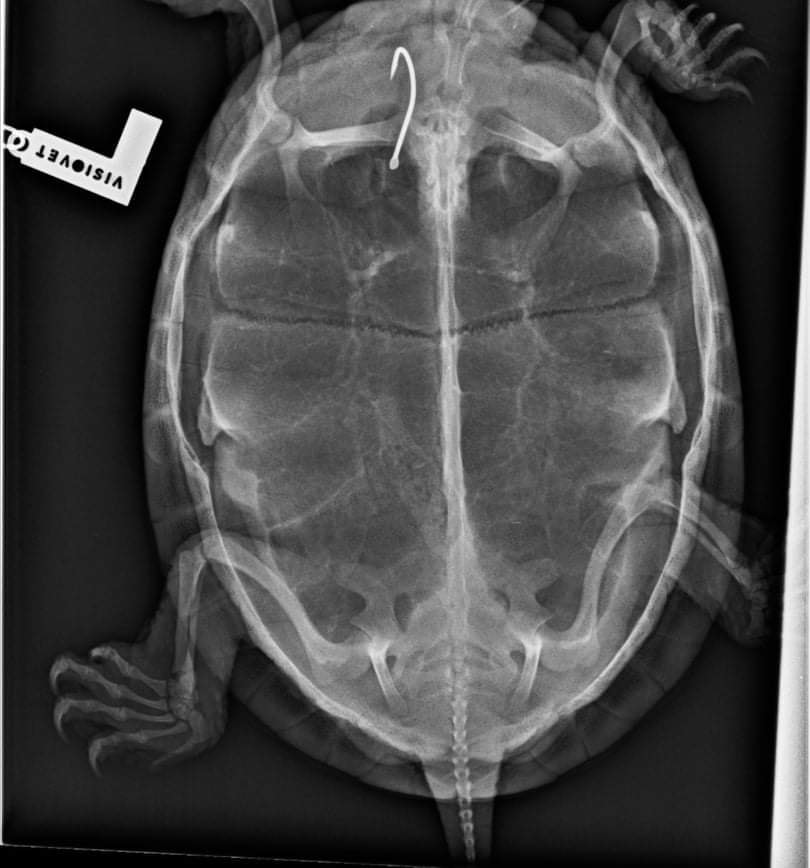

The case of Mocsi and the hook

We received a European pond turtle who swallowed a hook that got stuck in the esophagus. The X-ray and further examinations under anesthesia made it clear that the foreign body could only be removed using an endoscope or through an esophageal incision. In this case, despite a long struggle, the hook could not be removed with an endoscope, necessitating the esophageal incision, which finally gave the expected result.

After a few weeks of postoperative treatment and recovery, Mocsi was released into the wild in the Otter Park in Petesmalom.